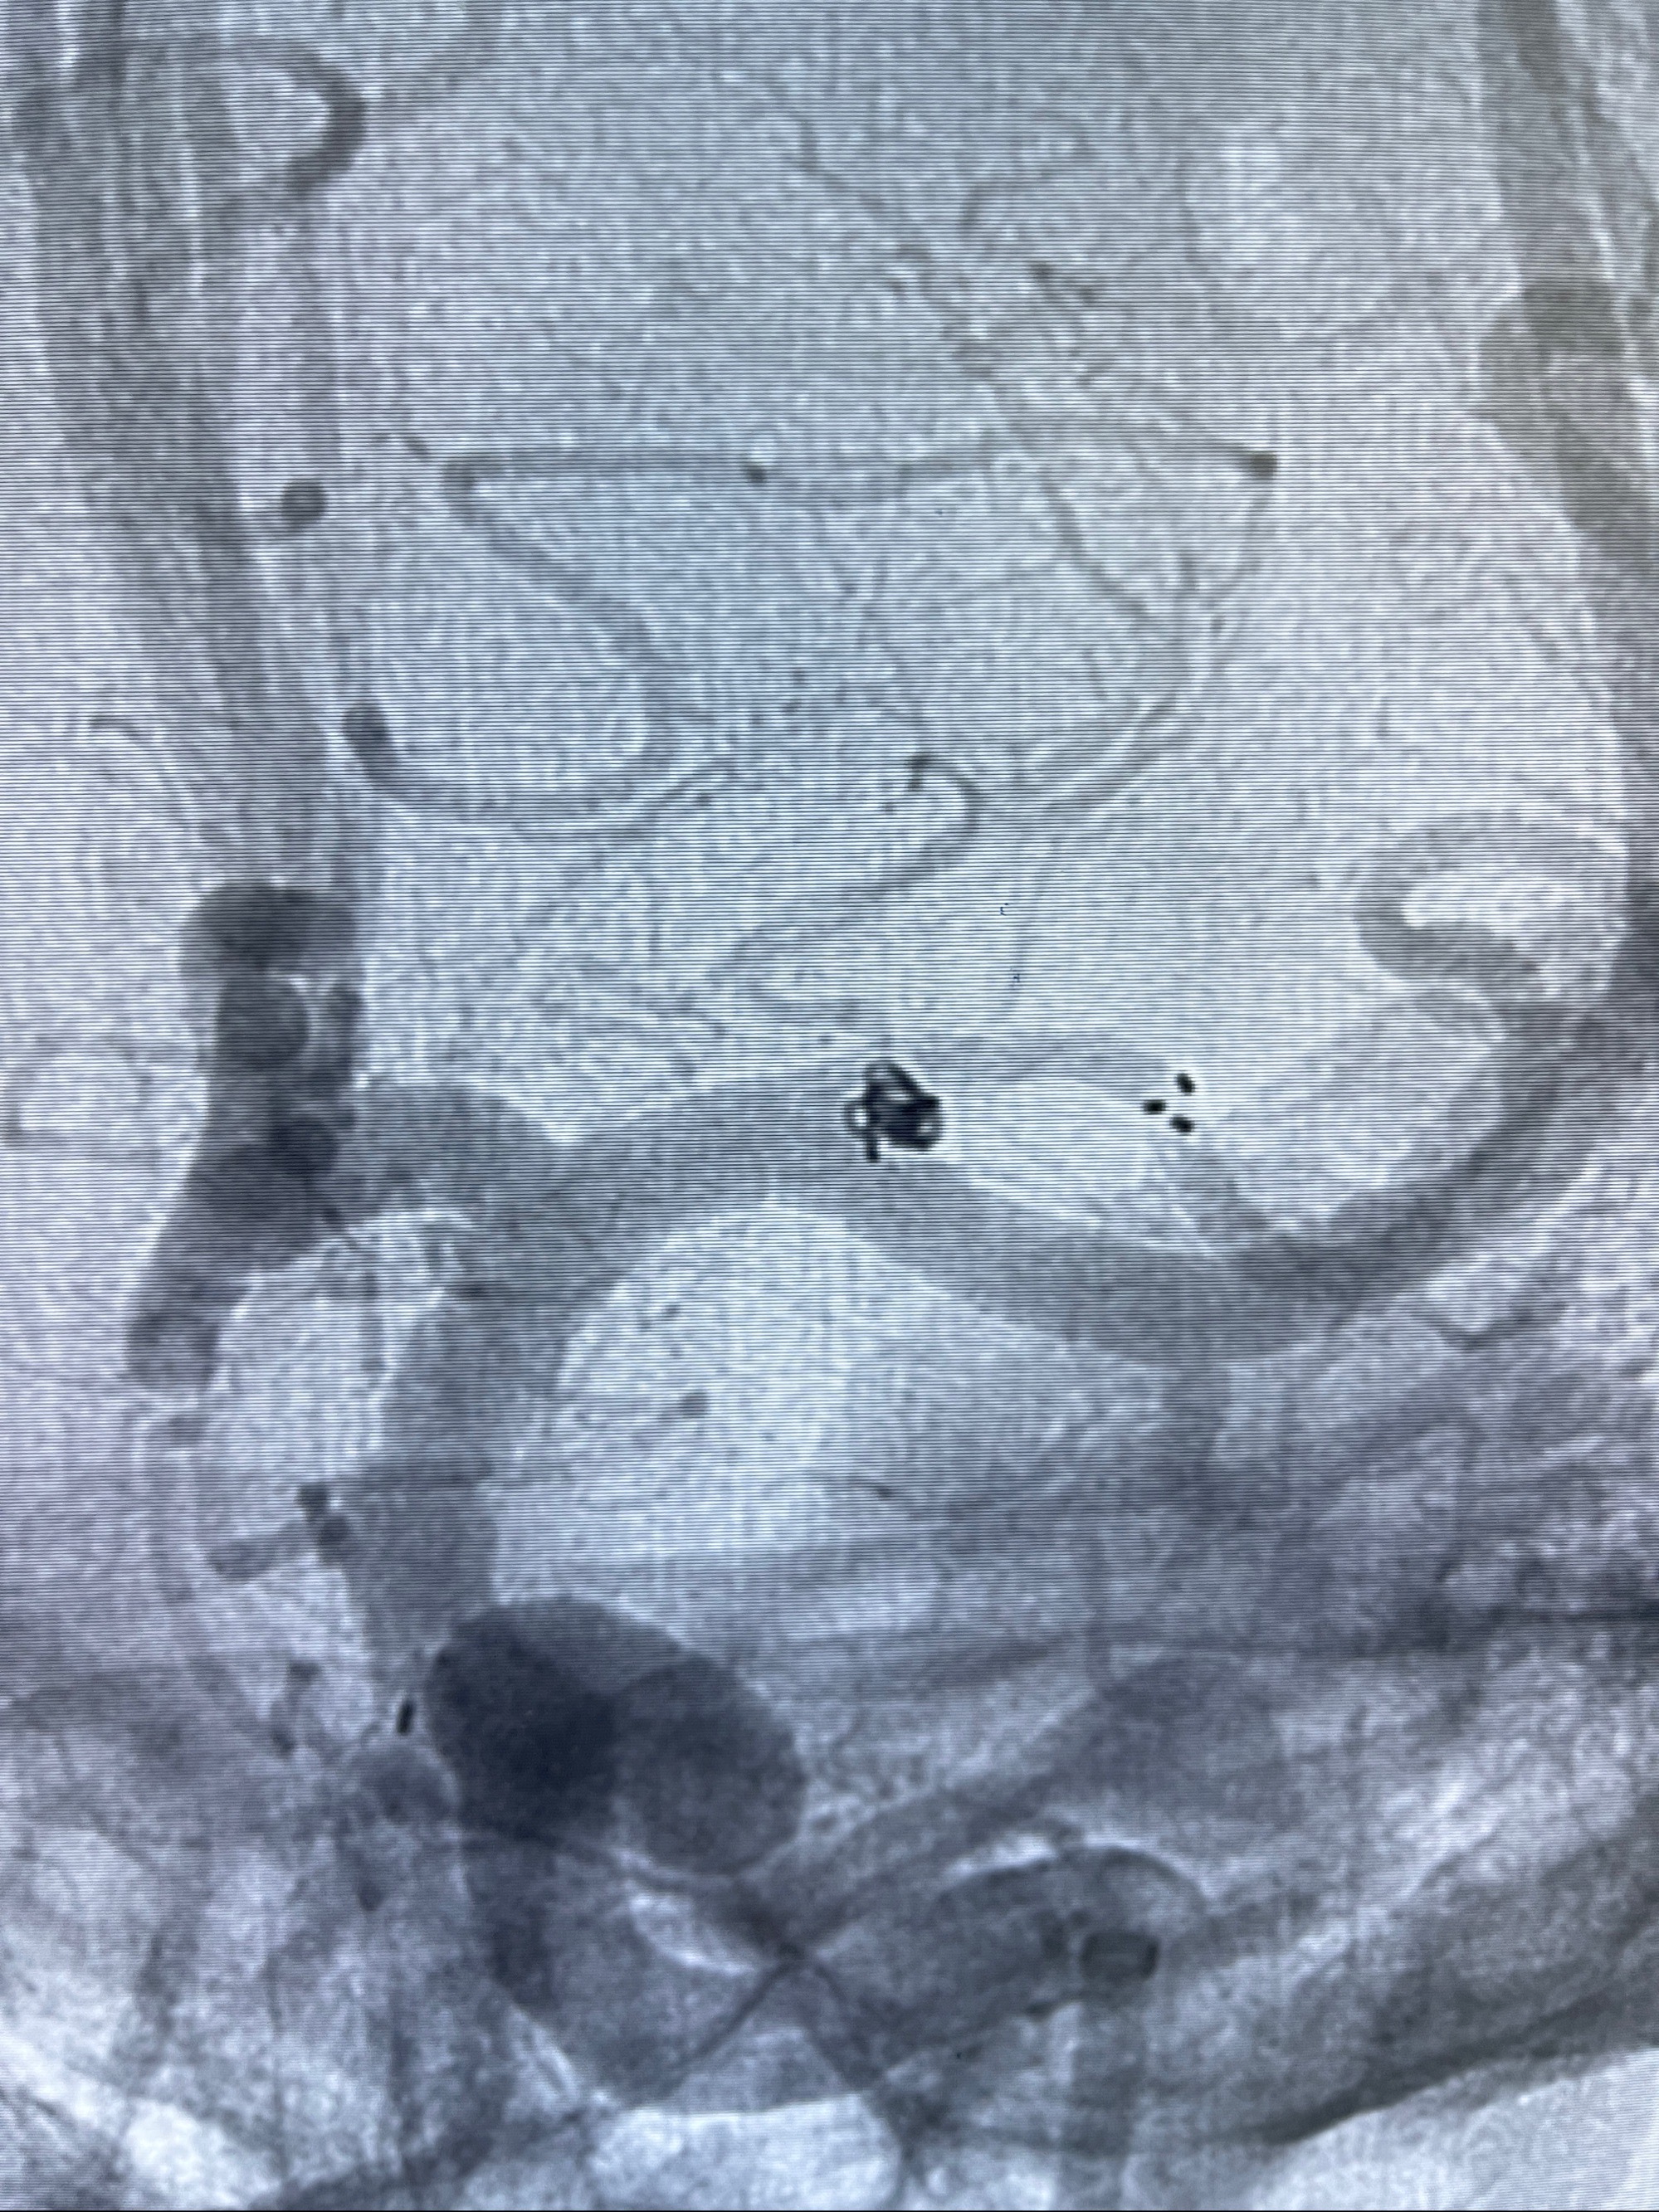

2023-08-14DSA:

左侧大脑中动脉动脉瘤,约2.6-2.8-3.4-2mm大小(瘤颈部、瘤体部、瘤高)

1.左侧大脑中动脉动脉瘤,约2.6-2.8-3.4-2mm大小(瘤颈部、瘤体部、瘤高)

2.外科手术夹闭or介入支架辅助栓塞